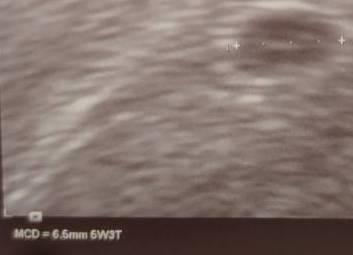

Die SSW wird erstmal immer vom ersten Tag der letzten Mens an gezählt (und ja, das macht bei unregelmäßigen oder extrem langen Zyklen extrem wenig Sinn). Offiziell wärst du am 25.11. also bei 4+3 gewesen (5. SSW). Dein hCG Wert von 36 spricht eher für ES+12 (3+5, 4. SSW). Wenn bei der ersten Vorsorgeuntersuchtung ein US gemacht wird, wird die Schwangerschaft dann anhand der Messwerte (zurück) datiert. In den ersten Wochen wachsen Fruchthöhle und Embryo relativ gleich, schallt man also z.B. in der 7./8. SSW schaut man, wie der Entwicklungsstand ist und datiert dann danach die Schwangerschaft "richtig". Vermisst dein Arzt per US die Fruchthöhle, spuckt das Gerät automatisch einen Stand aus (auf meinem US z.B. 5+3), danach wird dann datiert (entweder gleich oder erst bei der nächsten Kontrolle, das scheint so ein bisschen Geschmackssache zu sein, manche datieren nur einmal anhand der Messwerte, andere datieren im Verlauf nochmal um). Im großen Ganzen macht es keinen riesigen Unterschied, ob du Freitag bei 4+3 oder 3+5 warst. Über die 40 Wochen gleicht sich das alles aus (zwischen zwei Wochen vor ET und zwei Wochen nach ET ist ja quasi alles "gleich"). Einen Unterschied macht das höchstens, wenn man in der Frühschwangerschaft schallt, weil fünf Tage im Zweifel den Unterschied machen können, ob man z.B. schon einen Herzschlag sehen sollte oder ob ohne noch völlig im Rahmen ist. Wenn du frühestens in 4 Wochen zum ersten US gehst, sollte das aber am Ende auch keinen Unterschied machen (der Stand von 7+5 und 8+3 sollte relativ gleich sein).

Bild zu